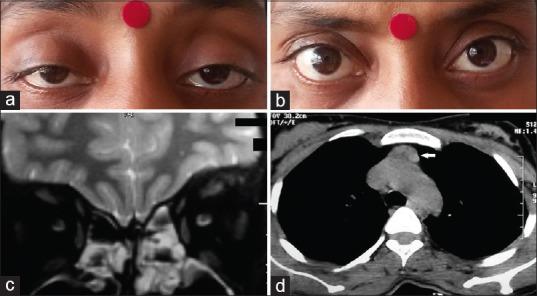

Graves' disease (GD) is characterized by a hyperfunctioning thyroid gland due to stimulation of the thyroid-stimulating hormone receptor by autoantibodies directed against it. Apart from thyrotoxicosis, other clinical manifestations include ophthalmopathy, dermopathy, and rarely acropachy. GD is an organ-specific autoimmune disorder, and hence is associated with various other autoimmune disorders. Myasthenia gravis (MG) is one such disease, which is seen with patients of GD and vice versa. Though the association of GD and myasthenia is known, subtle manifestations of latter can be frequently missed in routine clinical practice. The coexistence of GD and ocular MG poses a significant diagnostic dilemma to treating physicians. The ocular manifestations of myasthenia can be easily missed in case of GD and falsely attributed to thyroid associated ophthalmopathy due to closely mimicking presentations of both. Hence, a high degree of the clinical vigil is necessary in such cases to appreciate their presence. We present a similar case which exemplifies the above said that the clinical challenge in diagnosing coexistent GD and ocular myasthenia.

格雷夫斯病(GD)的特征是由于针对促甲状腺激素受体的自身抗体刺激,导致甲状腺功能亢进。除了甲状腺毒症外,其他临床表现还包括眼病、皮肤病,很少见的还有杵状指。GD是一种器官特异性自身免疫性疾病,因此与各种其他自身免疫性疾病有关。重症肌无力(MG)就是这样一种疾病,在GD患者中可见,反之亦然。虽然GD与重症肌无力的关联是已知的,但在常规临床实践中,后者的细微表现常常被遗漏。GD与眼肌型重症肌无力的共存给治疗医生带来了重大的诊断难题。在GD的情况下,重症肌无力的眼部表现很容易被遗漏,并由于两者表现相似而被错误地归因于甲状腺相关性眼病。因此,在这种情况下需要高度的临床警惕性来识别它们的存在。我们呈现了一个类似的病例,例证了上述诊断共存的GD和眼肌型重症肌无力时的临床挑战。